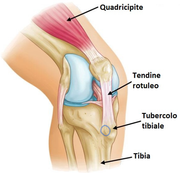

Metto una foto con un cerchietto in blu per far capire dove mi fa male, esattamente dove si inserisce il tendine rotuleo, l'apofisi tibiale, sulla parte mediale. Oltre alla corsa faccio sporadicamente basket, quest'ultimo in particolare esacerba particolarmente il dolore, ma anche la corsa purtroppo. Tre ortopedici mi hanno dato 3 pareri diversi, Osgood Schlatter, tendinite inserzionale del rotuleo e tendinite della zampa d'oca, tra l'altro tutti e tre a turno confutando le altre diagnosi. Mi fa male al tatto se premo in quel punto, e dopo la corsa faccio fatica a salire/scendere le scale e a rialzarmi dopo essere stato seduto. Da ottobre a 2 giorni fa sono stato a riposo, facendo solo esercizi di rinforzo in isometria. Ho pure fatto 4 sedute di onde d'urto dove sembrava fosse migliorato, non faceva male salendo/scendendo le scale e al tatto era diventato un fastidio; ieri sono andato a correre, alternando un minuto di corsa a uno di camminata, in totale 30 minuti. Dopo due ore era già riapparso il dolore con le scale e al tatto, e tutt'ora continua. Qualcuno ha sofferto qualcosa di simile? Conoscete ortopedici ferrati sull'argomento, magari che seguono squadre sportive, zona Roma?